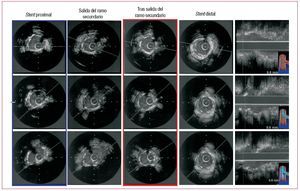

En todos los pacientes se consiguió el éxito inicial del procedimiento. En 1 (4%) caso hubo que implantar un segundo stent en el RS por obtener un resultado subóptimo tras la dilatación. En las tablas 3 y 4 se resumen los hallazgos ultrasónicos en cada estado de los distintos segmentos analizados. En el segmento proximal del stent y a nivel de la salida del RS se produce un incremento significativo del área y una pérdida de la geometría del stent tras el KB (figs. 2 y 3). En el segmento inmediato a la salida del RS se produce cierto grado de deformidad y pérdida de área tras dilatar el RS. Tras el KB se produce un leve incremento del área, aunque no llegaba a recuperarse hasta los valores basales a pesar de que el balón del stent era de mayor diámetro que el del RS y que el inflado se hacía a más atmósferas (12-14 AT en el VP, 6-8 AT en el RS). La figura 4 ilustra los cambios individuales en el área del stent tras cada estado en este segmento. En nuestro estudio no se encontró correlación alguna entre la angulación del RS y el grado de deformidad producido en el bajo rombo tras dilatar aisladamente el RS. En el stent distal, no se objetivaron diferencias significativas en ninguno de los estados.

Fig. 2. Estudio ultrasónico sobre el vaso principal tras implantar el stent, tras dilatar el ramo secundario y tras el kissing. En azul queda encuadrado el segmento proximal del stent, en el que se observa el incremento del área y la deformación producida tras el kissing en la geometría del stent. En rojo queda encuadrado el segmento distal a la salida del ramo secundario, que no varía en los distintos estados.

Si analizamos el segmento inmediato a la salida del RS, observamos que se produce una deformación en la geometría del stent (el IS pasa de 0,82 a 0,74; p < 0,01) y una discreta pérdida del área a dicho nivel, pasando de 5,9 ± 1,2 a 5,23 ± 1,1 mm2 (p < 0,05), lo que supone una pérdida del 12% del área del stent. Sin embargo, el espectro de deformación del stent en el bajo rombo es amplio, y varía desde casos en los que no se produce modificación alguna (fig. 2) a otros en que la deformación es más marcada (fig. 3). Quizá el diámetro del balón utilizado para dilatar el RS, el grado de angulación o la pata metálica por la que pasan la guía y el balón podrían modificar el grado de deformación del bajo rombo, y sería interesante determinar los posibles factores que influyen en dicha deformación en estudios ulteriores. En nuestro estudio no se encontró correlación alguna entre la angulación del RS y el grado de deformación en el bajo rombo (r = 0,32; p = 0,1). Además se dividieron los casos en ángulos > 60° y < 60°, y analizamos la pérdida de área del stent tras dilatar el RS y el grado de recuperación tras el KB; no se encontraron diferencias entre los dos grupos. En 6 (26%) casos, el área del stent osciló entre 4 y 5 mm2 y sólo 3 (14%) quedaron con un área luminal < 4 mm2, cifra por encima de la cual se considera poco probable que se produzcan defectos de perfusión14-18.